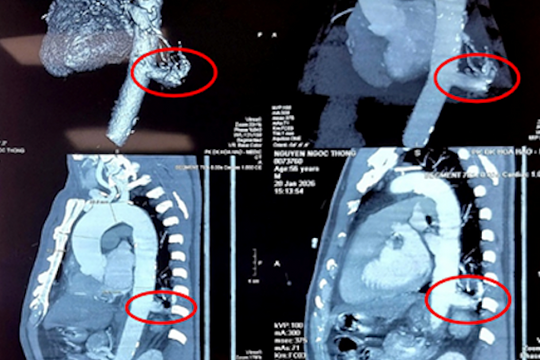

Ho ra máu kéo dài do khối phồng mạch máu hiếm gặp

Một bệnh nhân nam ngoài 50 tuổi ho ra máu kéo dài, đến Vinmec Smart City được phát hiện khối phồng mạch máu lớn trong lồng ngực, nguy cơ vỡ đe dọa tính mạng.